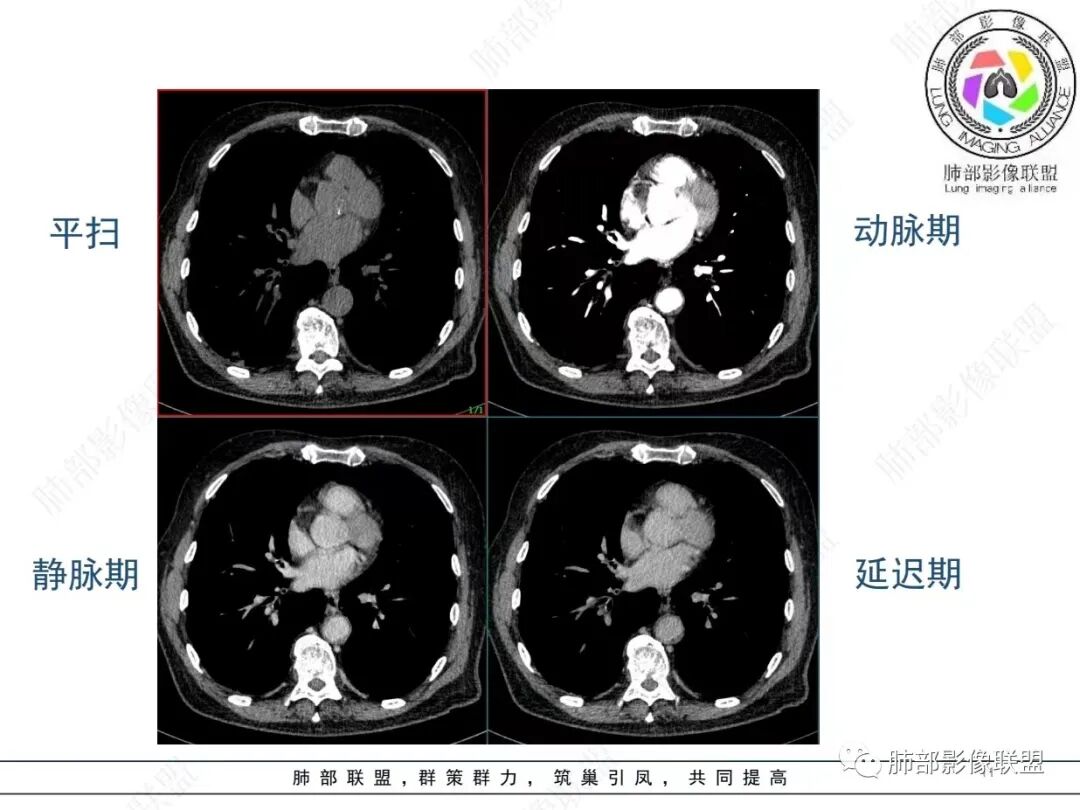

老年男性,发作性气喘,实验室检查白细胞增高。肺部影像表现:右肺胸膜下占位性病变,肺气肿背景,内部可见空腔/空泡影,周围可见小结节,增强动脉期明显强化,静脉期及延迟期强化减低,右侧肺门可见肿大淋巴结,有吸烟史,近年减少,首先考虑恶性肿瘤,肺小细胞癌/鳞癌,隐球菌作为鉴别诊断,病例穿刺活检。

老年男性,肺气肿病史,支气管束增粗,管壁增厚,右肺下叶后基底段胸膜下肿块,土豆征,边界清,有膨隆,小支气管边缘阻断,见集血管束征,肿块强化明显(快进快出特点),并偏心空洞,胸膜下栽赃,周围肺结构破坏(蜂窝状影表现),右肺门淋巴结转移肿大,血管内皮生长因子偏高,肿块与小支气管,血管束关系密切,强化特点,定恶性肺肿瘤,小细胞Ca。

右肺下叶胸膜下结节,呈山丘状,生长在慢支肺气肿间质纤维化的基础上,边缘相对光滑清晰,右肺门淋巴结肿大,强化呈速升速降,老年男性,吸烟史,考虑小细胞肺癌,鉴别隐球

恶性明确(右肺门淋巴结明显肿大,中心坏死,坏死边界不清楚,胸膜下馒头样肿块,血管集束,支气管阻塞,动脉期明显强化,内部明确的供血血管提示肿瘤细胞密集,局部坏死边界不清,强化快进快出,邻近胸膜强化呈胸膜尾征,提示胸膜受侵),病理符合周围性低分化鳞癌(老年男性,长期吸烟史,肿块强化明显,快进快出,坏死边界不清楚,阻塞性炎症及阻塞性肺气肿,肺门淋巴结肿大,坏死,邻近支气管壁增厚支持粘膜下侵润生长),白细胞总数高,动脉期强化那么明显,腺癌合并感染倒是要高度警惕。

老年男性,吸烟史+肺气肿背景,右下肺胸膜下肿块(坏死+内部血管影+快进快出),右侧肺门淋巴结肿大,考虑:恶性、鳞?高级别腺待排(总体感觉偏软)。

男,80,发作性气喘半年,加重1天。长年大量吸烟史。肺部CT:肺气肿背景,右肺胸膜下实性占位,处于外周大疱带与气肿带交界,山丘征,边缘膨隆,边界较清,血管集束,周围可见小结节。增强不均匀强化,内可见迂曲模糊血管影,右肺门、隆突下可见肿大淋巴结。首先考虑恶性肿瘤,小?鳞?鉴别PC、TB等。